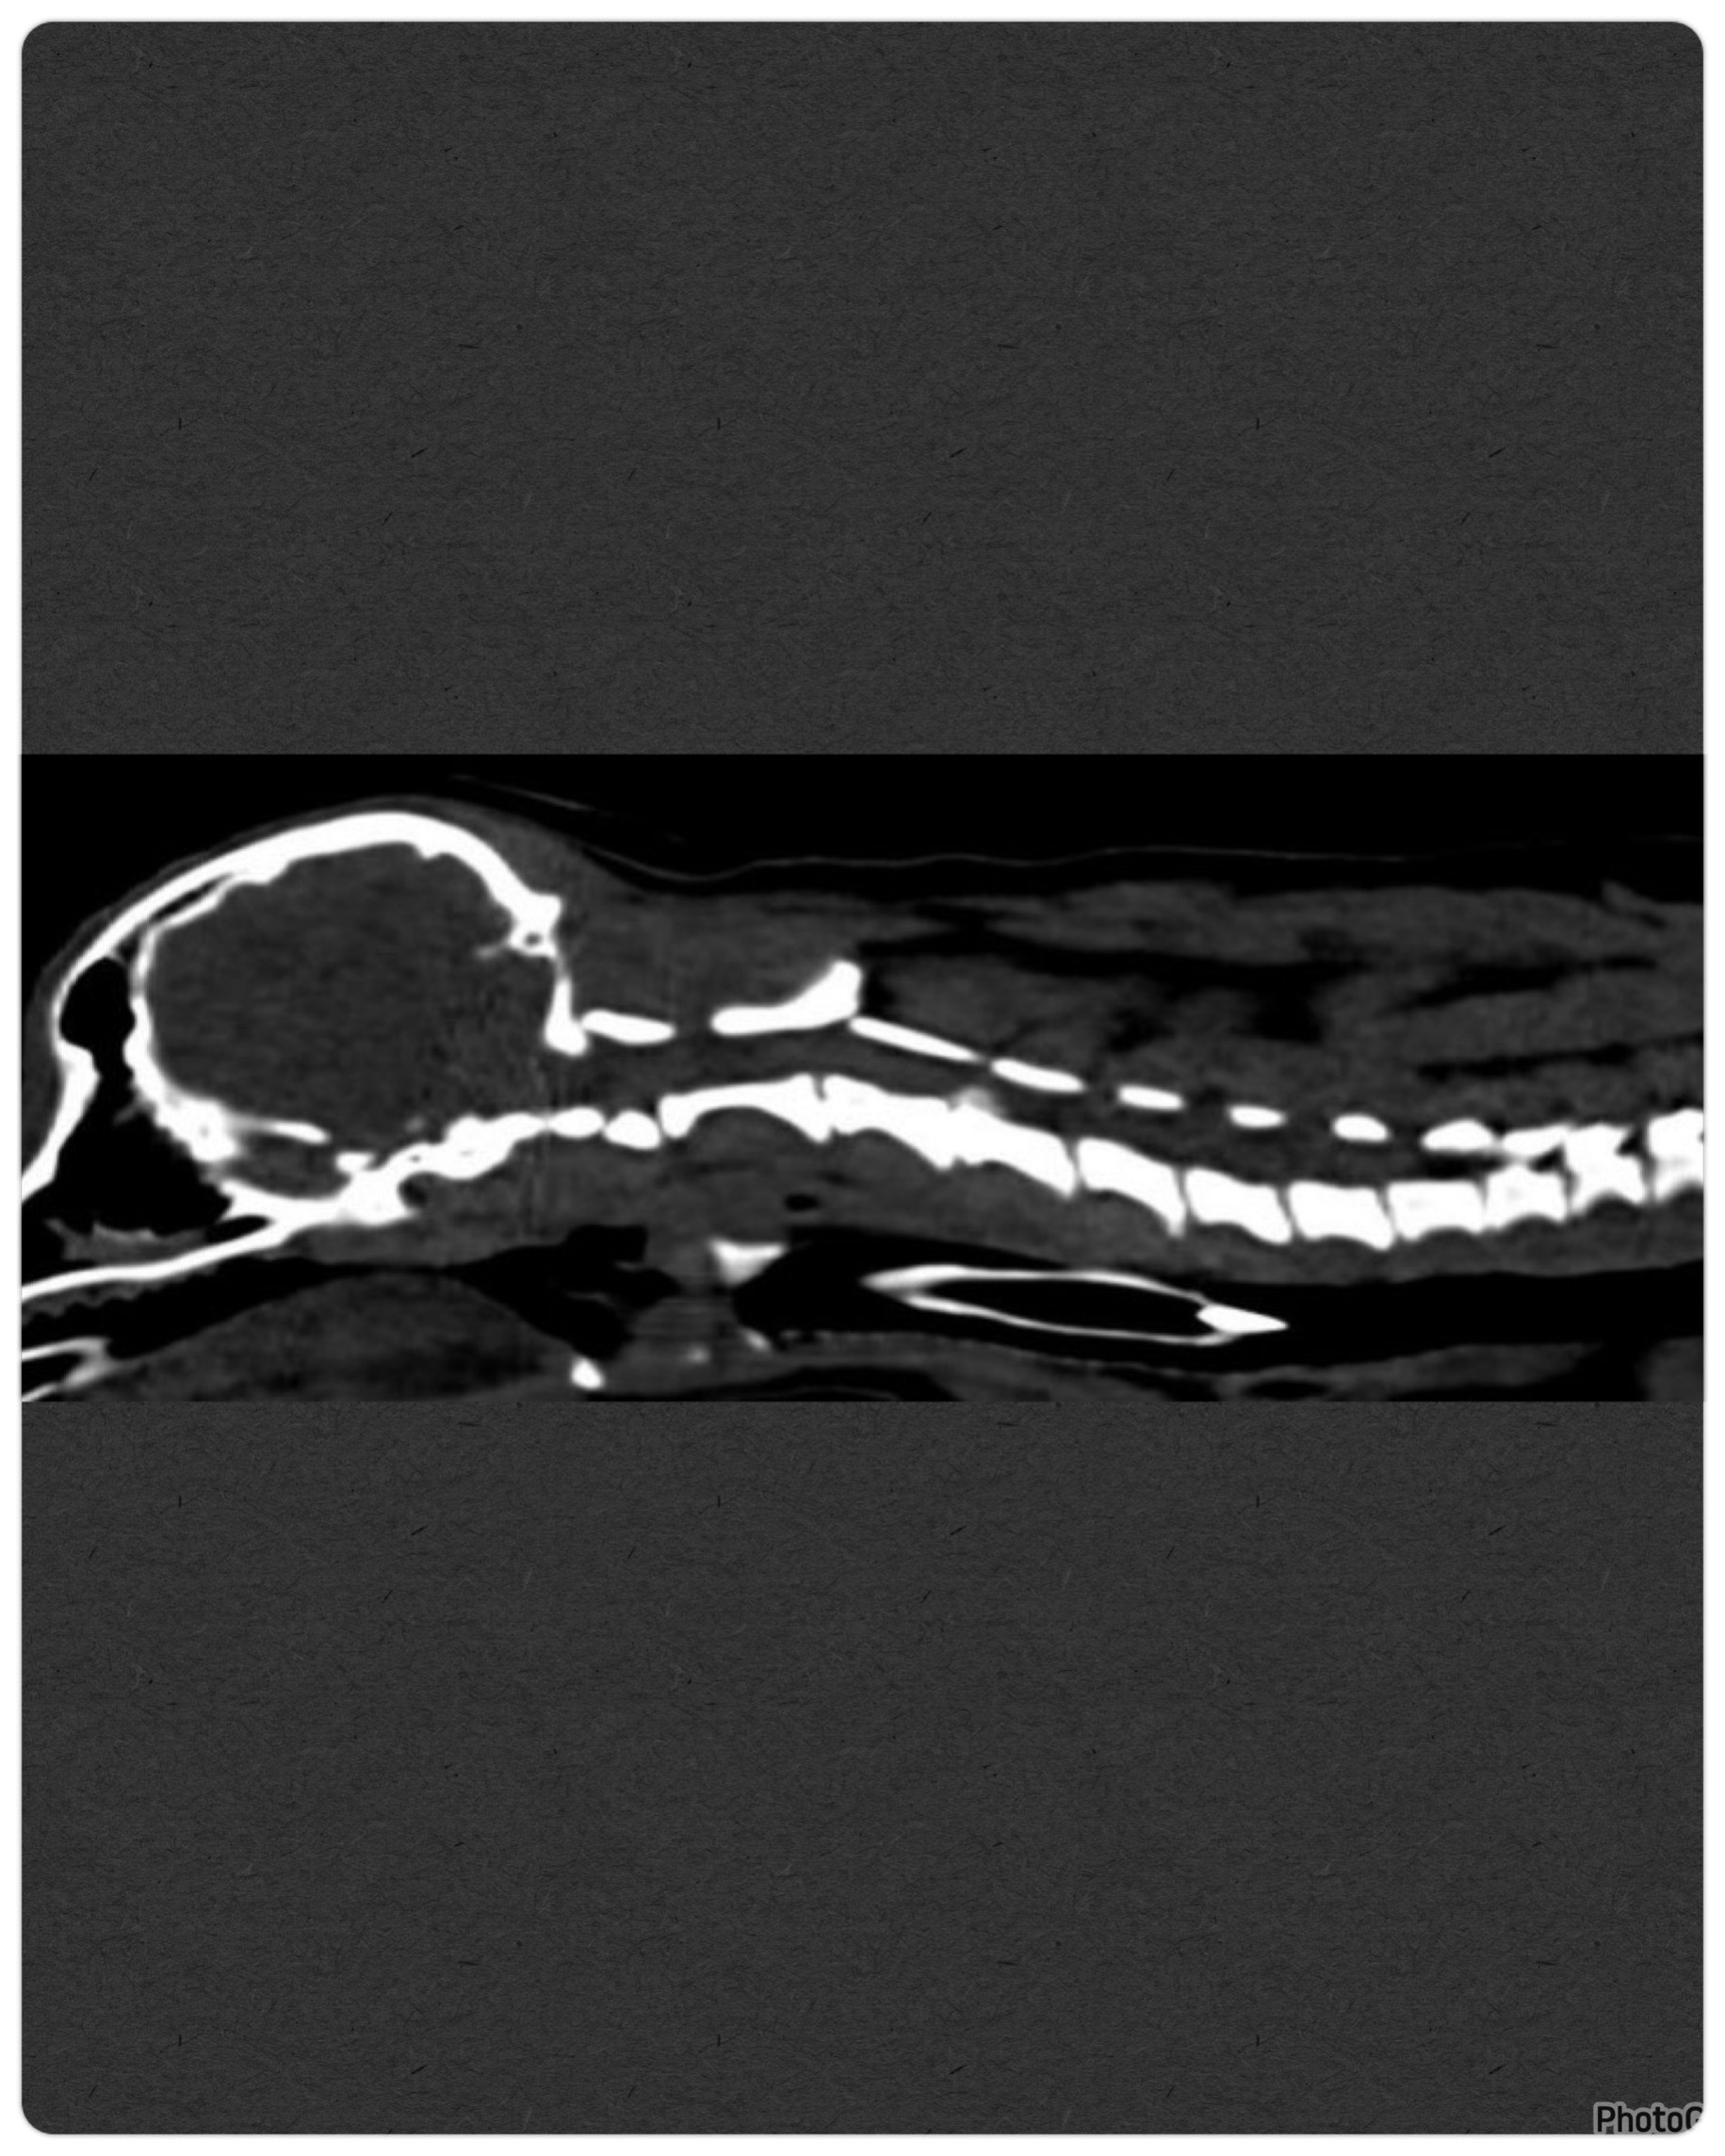

在醫師進行基礎的理學檢查及 Xray 影像後,並無發現明顯異常,給予止痛藥仍改善不佳,因此安排進階的電腦 斷層掃描,最終診斷為第三、四頸椎間之 IVDD,因椎間盤礦化嚴重壓迫脊髓導 致疼痛難耐。

在和飼主溝通過內外科治療個別的優缺點後,考量到噹噹除了疼痛 之外,並無步態異常,最終決定以中獸醫/針灸方式,協助改善病情。

只經過四 次針灸療程,其中包含乾針、電針及水針,並搭配中藥的服用,噹噹原先症狀即 獲得很大的改善,無再出現異常疼痛感,後續皆以中藥做保養。